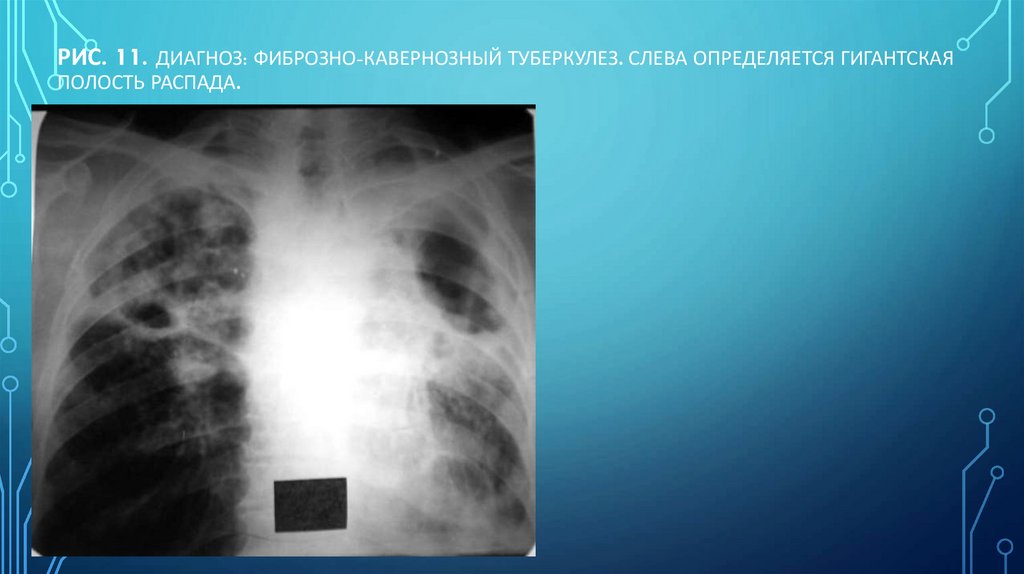

Рис. 11. Диагноз: Фиброзно-кавернозный туберкулез. Слева определяется гигантская полость распада.

118. Рис. 11. Диагноз: Фиброзно-кавернозный туберкулез. Слева определяется гигантская полость распада.

РИС. 11. ДИАГНОЗ: ФИБРОЗНО-КАВЕРНОЗНЫЙ ТУБЕРКУЛЕЗ. СЛЕВА ОПРЕДЕЛЯЕТСЯ ГИГАНТСКАЯ

ПОЛОСТЬ РАСПАДА.

Н.С. ВОРОТЫНЦЕВА, С.С. ГОЛЬЕВ РЕНТГЕНОПУЛЬМОНОЛОГИЯ